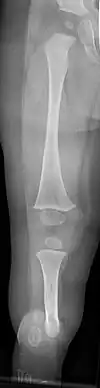

![]() | |

| a, b) Paley type 3c fibular hemimelia | |